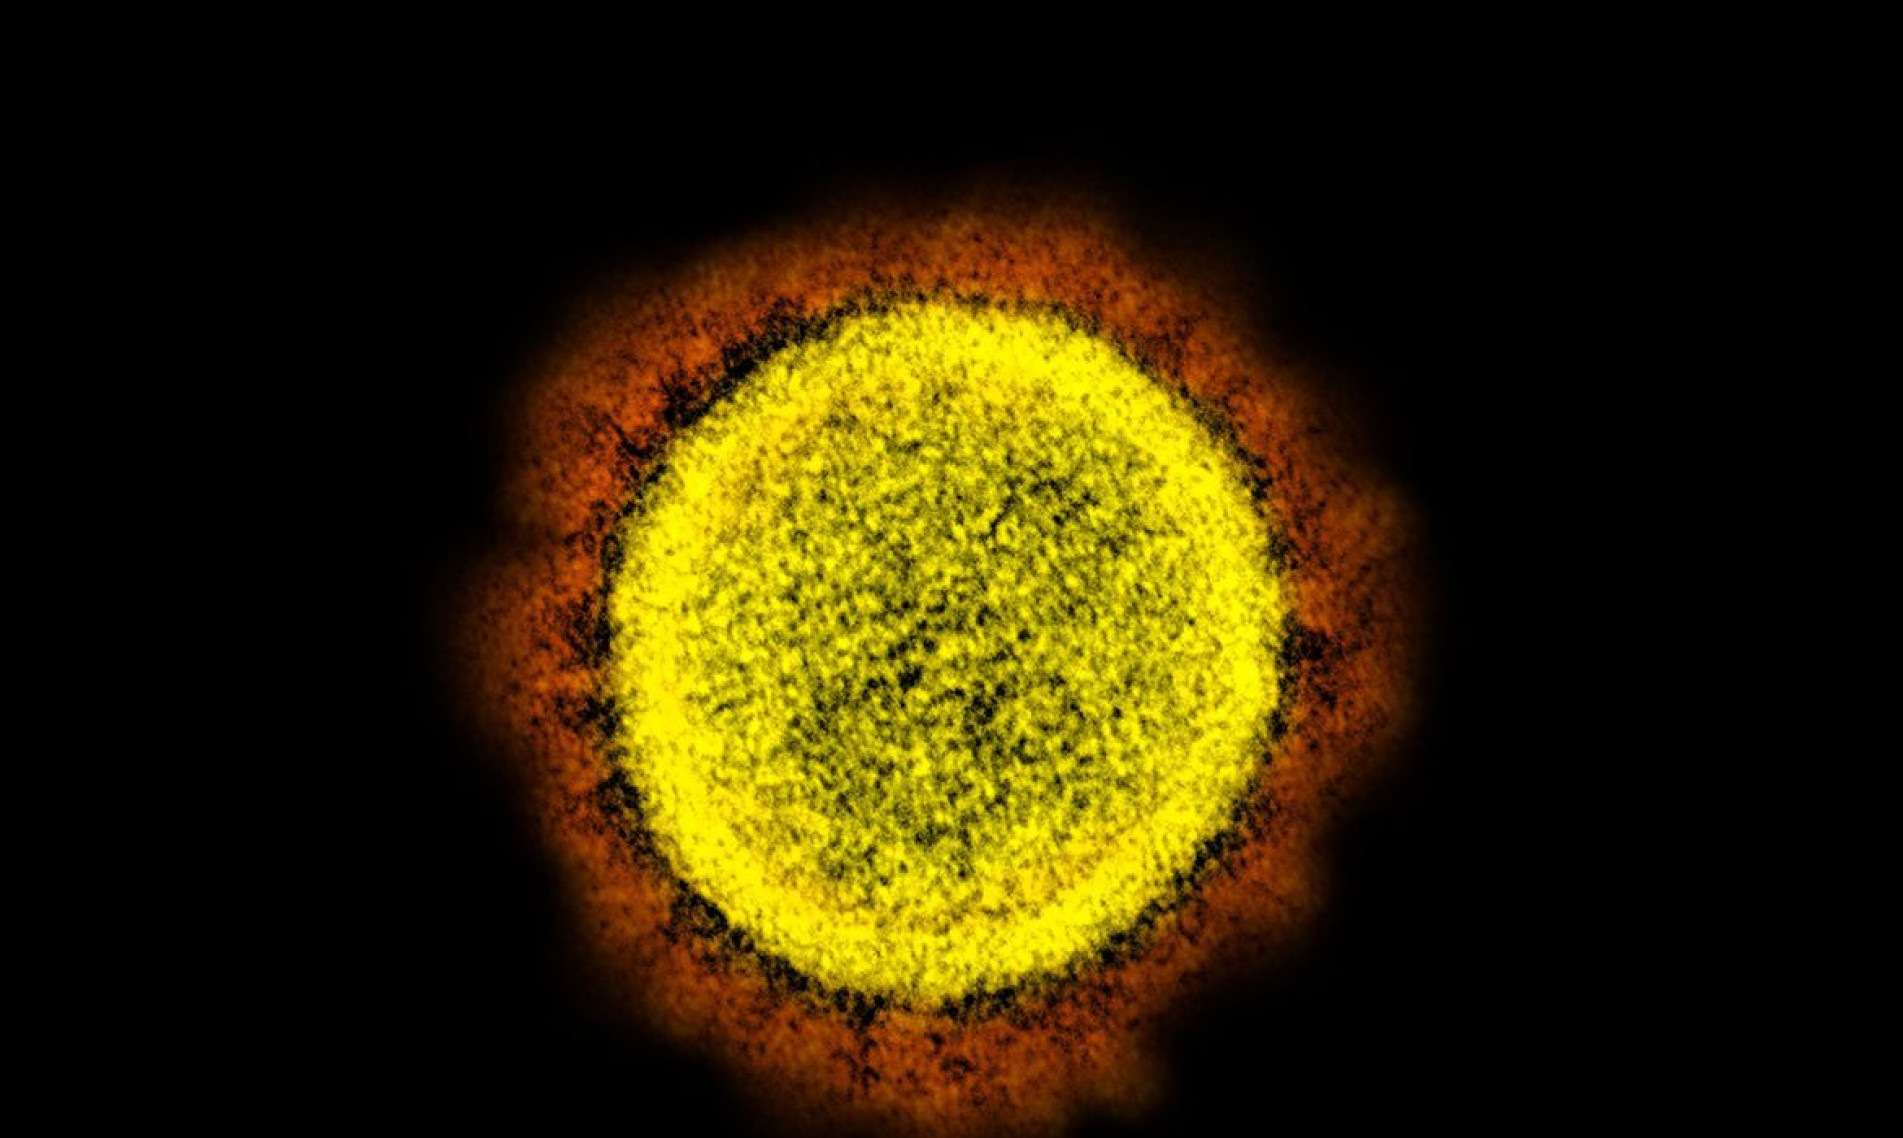

Número de casos confirmados da doença passa de 22,2 milhões

Com as 56 mortes registradas nos últimos três dias, das quais 28 entre sábado (31) e domingo (1º), o Brasil chega a 619.133 óbitos por Covid-19 desde o início da pandemia. Há ainda 2.817 óbitos em investigação.

O total de casos confirmados é de 22.293.228, já somados os 1.721 casos divulgados neste domingo (2) pelo Ministério da Saúde. Segundo a pasta, 21.581.717 pessoas já se recuperaram da doença.